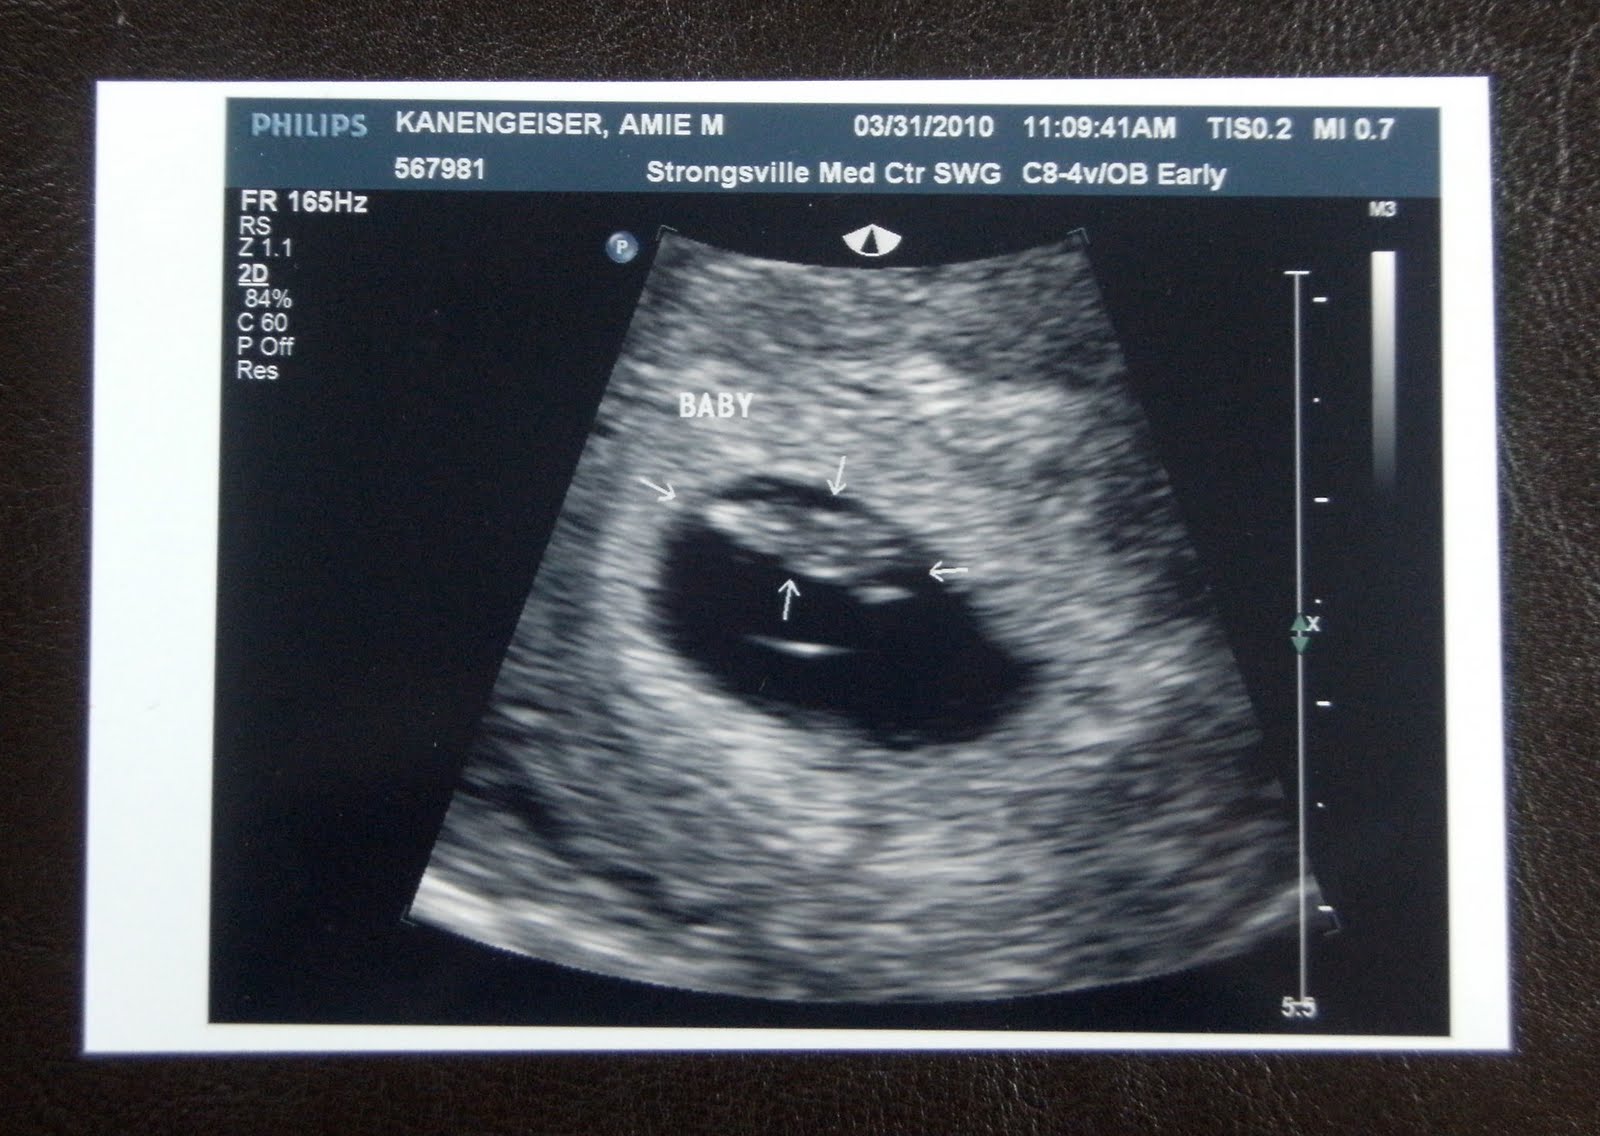

Yay!!! I had my first appointment this morning. Oh my goodness, I have been on pins and needles waiting for it! Well, the exam went wonderfully, everything looked great. But because of my resent history of loss, she sent me down for an early ultrasound to check for viability and to make sure we were on target for dating since my periods have been so irregular. Immediately the ultrasound tech found the little baby and it had a wonderful, strong heartbeat of 144 (it should be anywhere between 120-175, so we are right in the middle). I instantly started crying, I was just so, so happy. I will never forget that feeling!  I feel such a lightness in my heart. God is so good! Now my chance of a m/c went from 50/50 chance to a 3% chance. I'll take those odds!  Awesome. I am so happy!!!!!

It looks more like a smudge then a baby at this point- but it's there!!